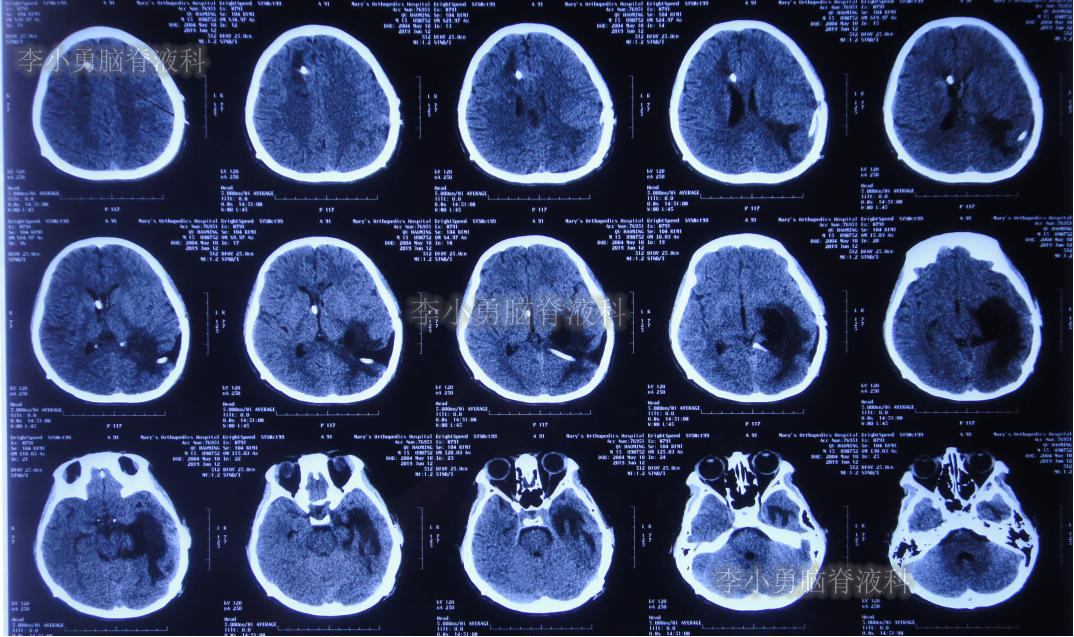

入院次日即2019年5月8日,进行了右侧脑室外引流术,并保留原来脑室外引流管(注:脑室内有两根管)。术后常规复查头颅CT(图-11)。

图-11:2019年5月9日头颅CT:引流出淡黄色脑脊液

入院当日行头颅CT(图-10):脑室内“动脉瘤切除术”后改变,术区可见引流管影,脑室扩大。

图-10:2019年5月7日头颅CT:引流术后,脑室扩大